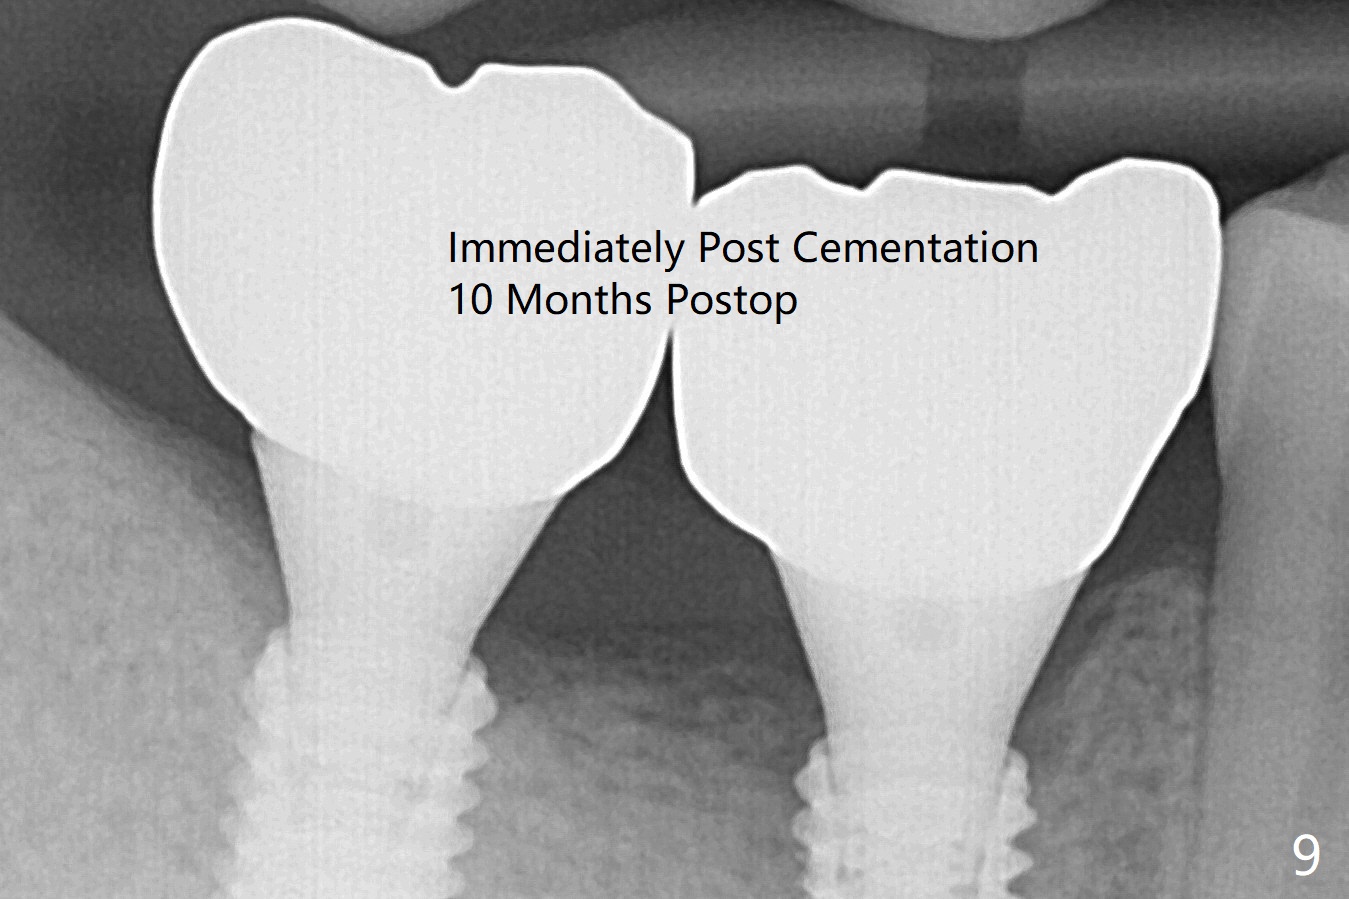

The implants at #30 and 31 remain asymptomatic 6 months post cementation (Fig.11, as compared to Fig.9 (immediately post cementation)).